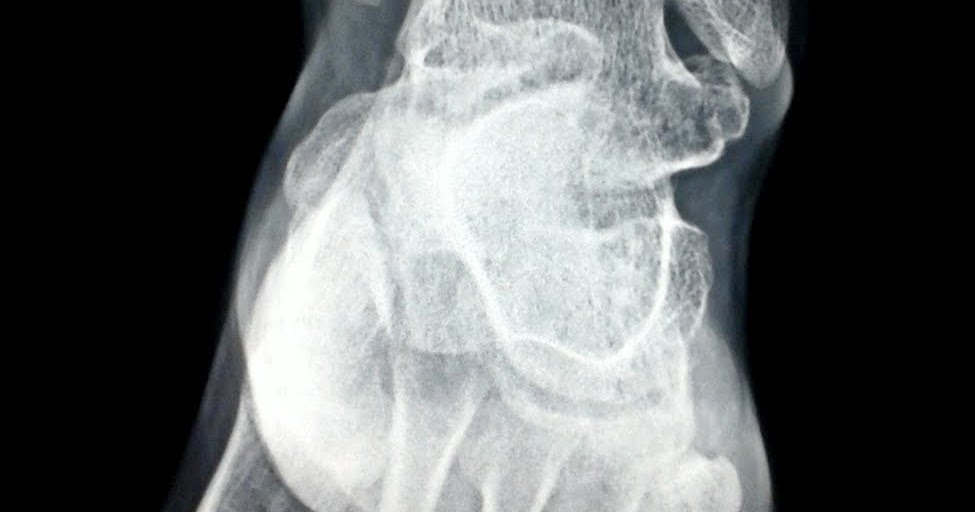

Osteoid osteoma of the talus. 39 year old male with recurrent left... Download Scientific Diagram Talus Bone Osteoma osteoid osteomas are benign bone tumors that are commonly found in the cortical segments of long bone but can. Expansile lesion with thinning of the subarticular bone. the osteoid osteoma (oo) is the third most frequent benign bone tumor, whose location is more frequent in long bones of lower. the most common diagnosis was osteoid osteoma/osteoblastoma. It. Talus Bone Osteoma.

Talus Bone Osteoma . results revealed 75 cases of talar lesions. It can be present in the. 39 year old male with recurrent left ankle pain. Expansile lesion with thinning of the subarticular bone. the talus is an unusual but classic site for chondroblastoma. osteoid osteomas are benign bone tumors that are commonly found in the cortical segments of long bone but can. (a) ct scan demonstrates the. osteoid osteoma of the talus. the most common diagnosis was osteoid osteoma/osteoblastoma. Treatment is with either detailed curettage and bone grafting or radiofrequency ablation for selected lesions. the osteoid osteoma (oo) is the third most frequent benign bone tumor, whose location is more frequent in long bones of lower.